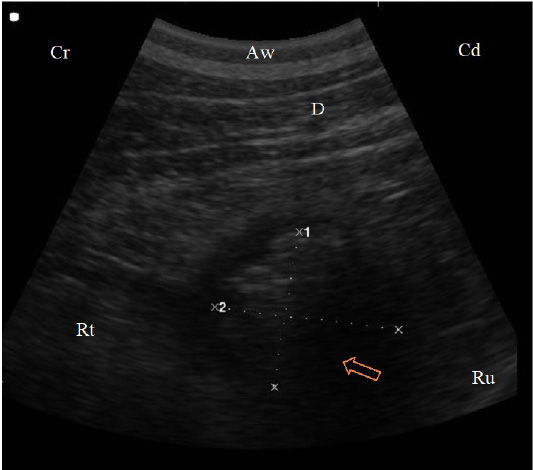

B. Mode sonogram in a case with reticular abscess (arrow) appeared as a circumscribed structure, 4.8 cm diameter, with echogenic wall and anechogenic to hypoechogenic content between the reticulum (Rt) and the diaphragm (D) imaged from the left 7th ICS, Aw: Abdominal wall, Cr: Cranial, Cd: Caudal.